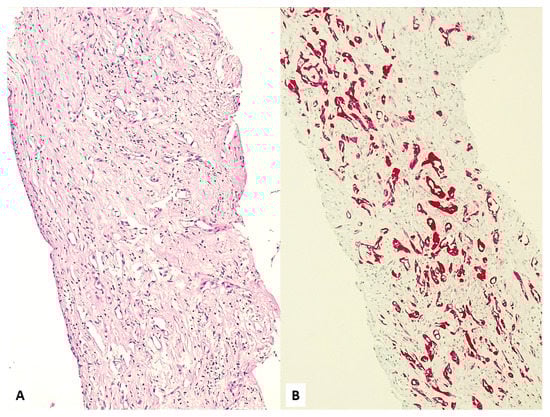

3. Unusual Radiological Presentation